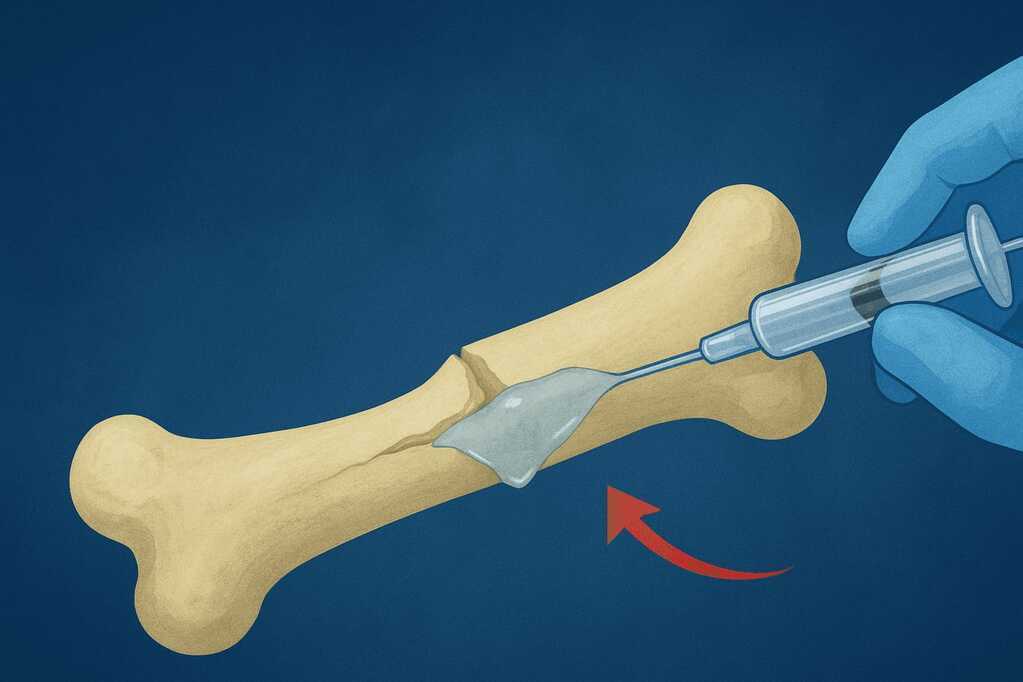

Tuy nhiên, nhóm nghiên cứu tại Đại học Chiết Giang (Zhejiang University) , thành phố Hàng Châu, Trung Quốc, vừa công bố rằng họ đã tìm ra một giải pháp đơn giản và nhanh chóng hơn rất nhiều: một loại keo dán y học có khả năng "hàn gắn" xương gãy trong thời gian chưa đầy 5 phút.

Theo bác sĩ Lin Xianfeng , chuyên gia phẫu thuật chỉnh hình tại Bệnh viện Sir Run Run Shaw (Hàng Châu), Bone-02 hoạt động vô cùng hiệu quả và dễ sử dụng. "Chúng tôi chỉ cần tiêm loại keo này vào vị trí gãy. Trong vòng khoảng ba phút, các mảnh xương sẽ được cố định chặt lại với nhau mà không cần can thiệp phẫu thuật phức tạp", ông Lin chia sẻ. Nhóm của ông cho biết Bone-02 đã được thử nghiệm thành công trong hơn 150 ca điều trị , bao gồm cả những trường hợp gãy cổ tay, chân và xương sườn.

Một trong những ca điển hình là bệnh nhân bị gãy cổ tay do tai nạn sinh hoạt. Thay vì phải phẫu thuật đặt nẹp kim loại, bác sĩ chỉ thực hiện một vết rạch nhỏ dài 3 cm, sau đó tiêm Bone-02 vào vị trí tổn thương.

Từ nguyên lý tự nhiên ấy, nhóm khoa học đã nghiên cứu cấu trúc hóa học của keo hàu và phát triển nên Bone-02 - một hợp chất tổng hợp có khả năng tạo liên kết cực mạnh giữa các mô xương mà vẫn tương thích sinh học với cơ thể người. Loại keo này không chỉ "dính" trong môi trường khô mà còn hoạt động hiệu quả trong điều kiện ẩm ướt, điều vốn là trở ngại lớn đối với hầu hết các loại keo y học hiện nay.